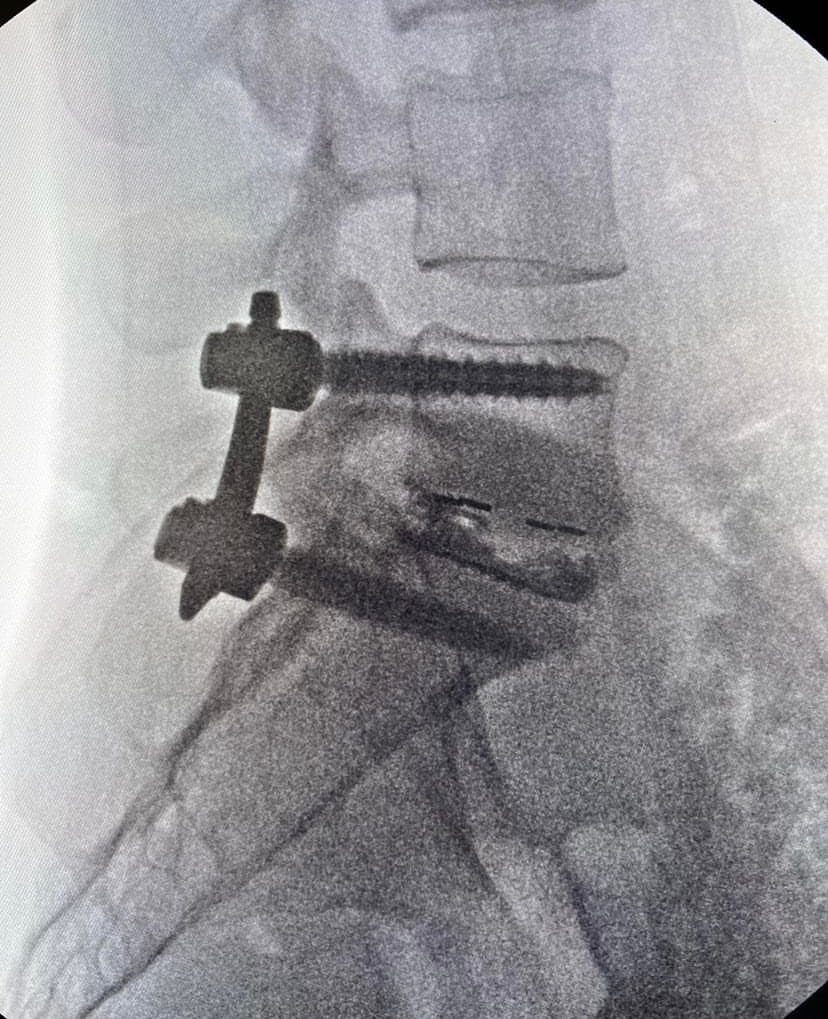

- 4 Screws and a Cage

4 Screws and a Cage

4 Screws and a Cage to separate the vertebrae and realign the spine